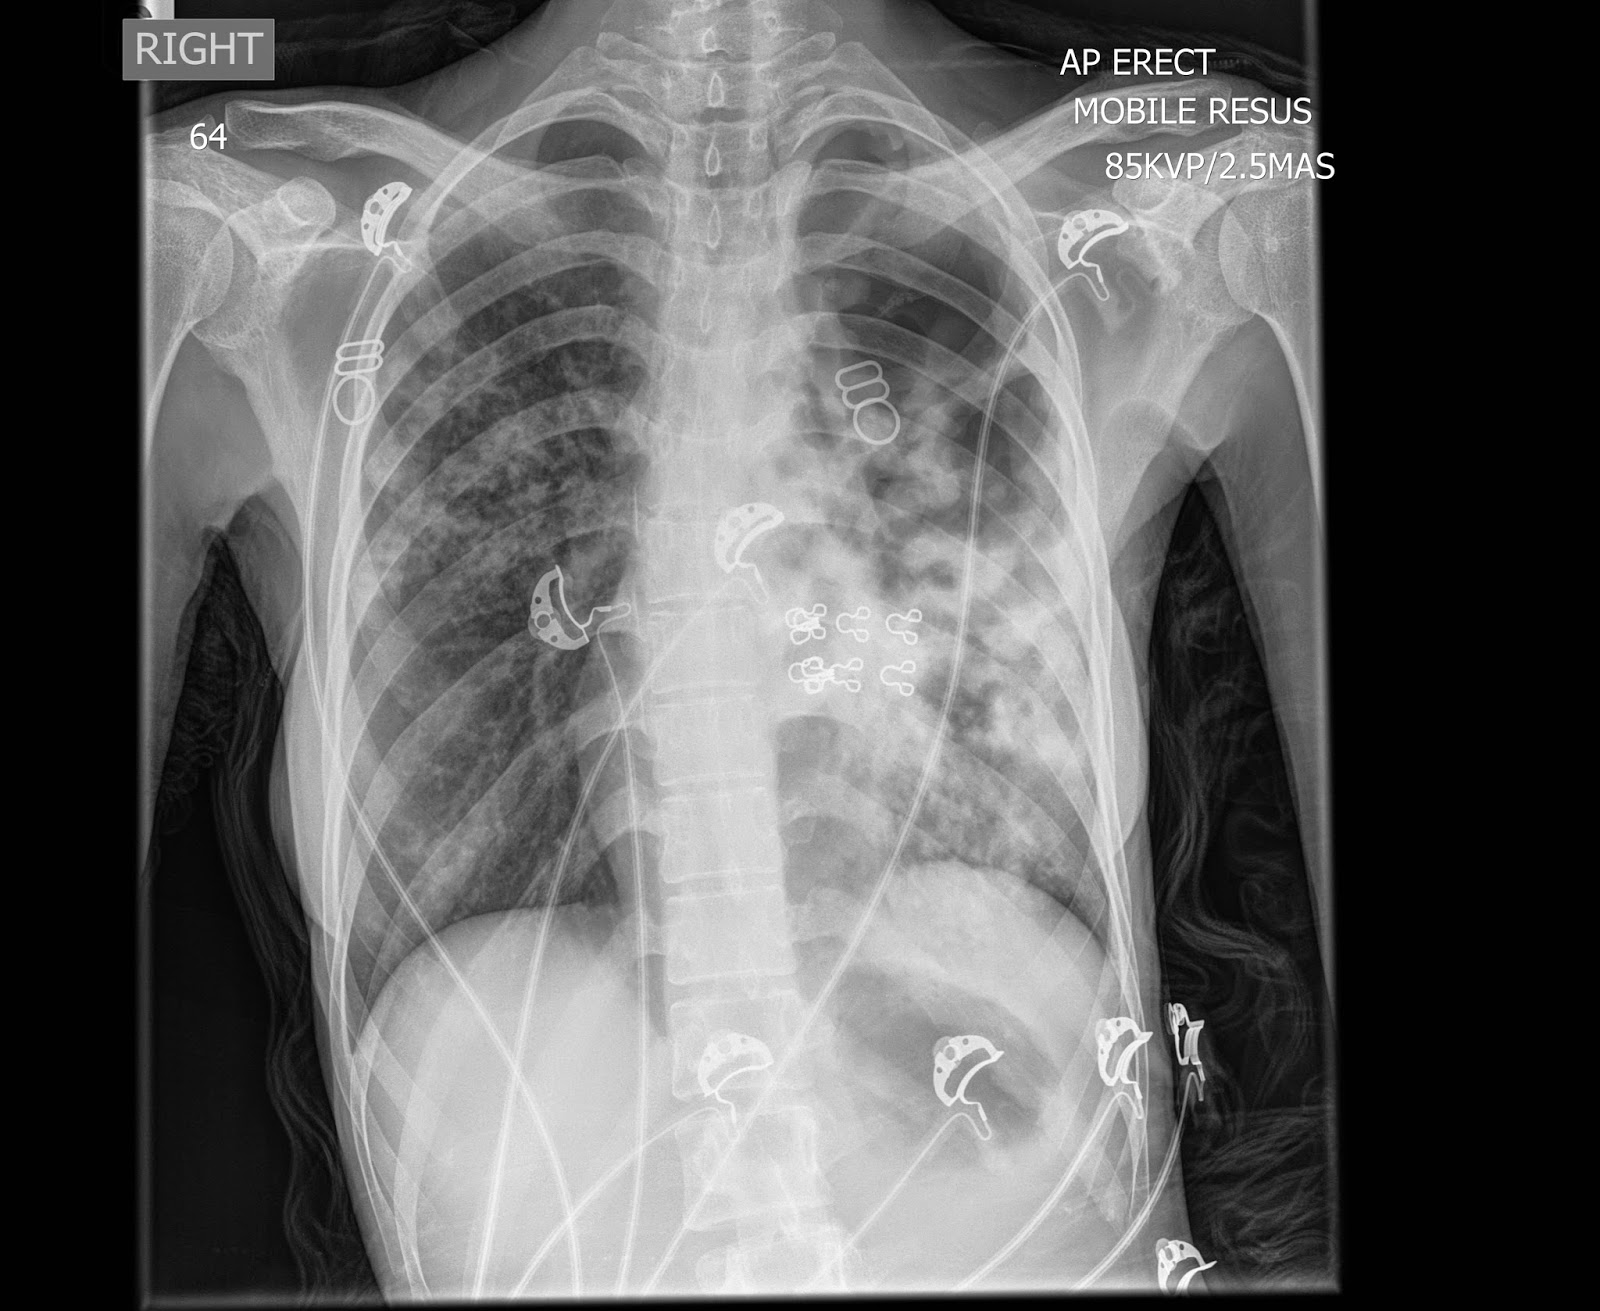

From www.slideserve.com

PPT SHORTNESS OF BREATH PowerPoint Presentation ID5093211 What Does A Chest X-Ray Show For Shortness Of Breath During a pulmonary function test, you blow into a device called a spirometer, which measures how much. It might feel like your chest is tight, you’re gasping for air or you’re working harder to breathe. There are no visible nodules, tumors or masses. Dyspnea, or shortness of breath, is the feeling that you can’t get enough air into your lungs.. What Does A Chest X-Ray Show For Shortness Of Breath.